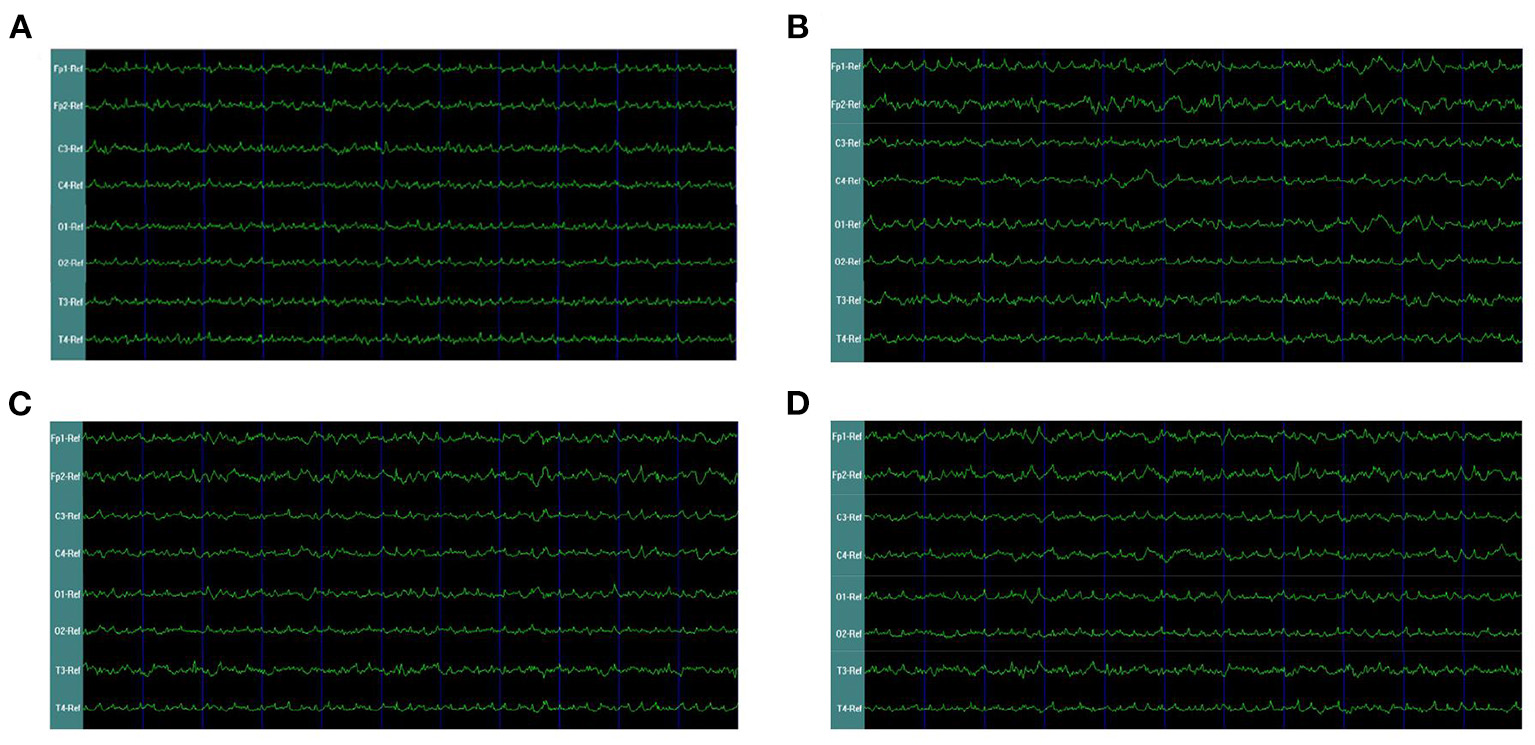

In our second phase of the research, the rat model of left side TBI was built. The EEG pattern is shown in Figure 4. We found that the gamma oscillation of rats with left TBI significantly decreased in cortex electrodes Fp1 (P < 0.001), T3 (P < 0.001), C3 (P < 0.001), and O1 (P = 0.002) (Figure 5A, Table 3). Similarly, after receiving 1 week of 40 hz Blue LED intervention, the gamma oscillation of rats significantly increased in these cortex electrodes Fp1 (P = 0.001), T3 (P < 0.001), C3 (P = 0.001), and O1 (P = 0.001), comparing with the TBI(L,7d) group (Figure 5B, Table 4) and this result was completely consistent with that of right side TBI rats.

Figure 4

EEG waveforms of left-side TBI in rats. (A) EEG waveforms of control subgroup (B) EEG waveforms recorded immediately after TBI (C) EEG waveforms of 7 days after TBI without treatments (D) EEG waveforms of TBI after 7-days treatment of 40 hz Blue LED.